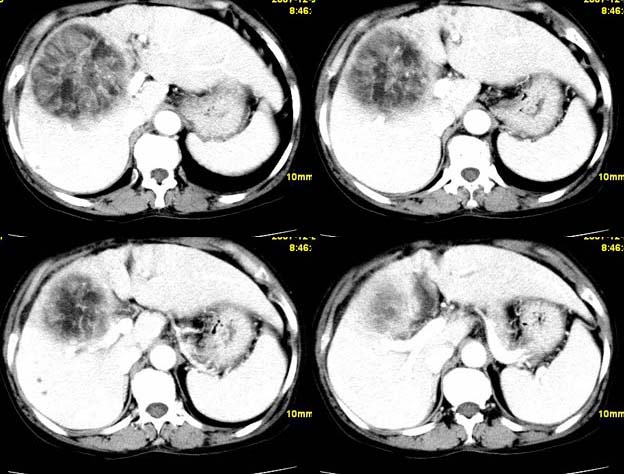

肝血管平滑肌瘤脂肪瘤可能性大。

支持肝血管平滑肌脂肪瘤可能性大。

肝血管平滑肌脂肪瘤

考虑1肝细胞腺瘤可能性大(病灶周围有透明环影)恶变?2血管平滑肌脂肪瘤?建议穿刺病检.

肝血管平滑肌脂肪瘤可能性大,不除外包虫病

肝血管平滑肌脂肪瘤可能性大;原发型肝癌待排。